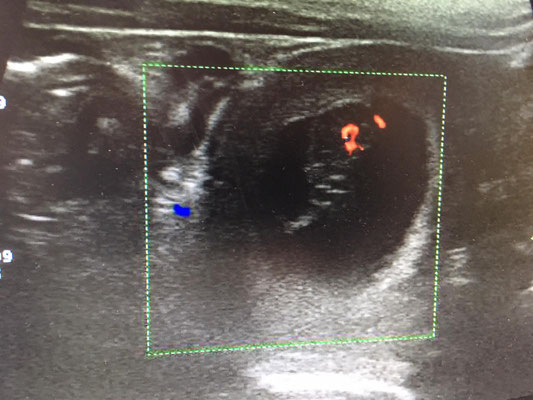

Die Trächtigkeit wurde mittels Ultraschall bestätigt. Jetzt ist es amtlich. Mitte Januar wird der B-Wurf "vom Wodangrund" erwartet. Auch optisch ist eine Veränderung erkennbar. Die Zitzen haben sich etwas vergrößert und ein "kleiner Bauch" ist wahrnehmbar.